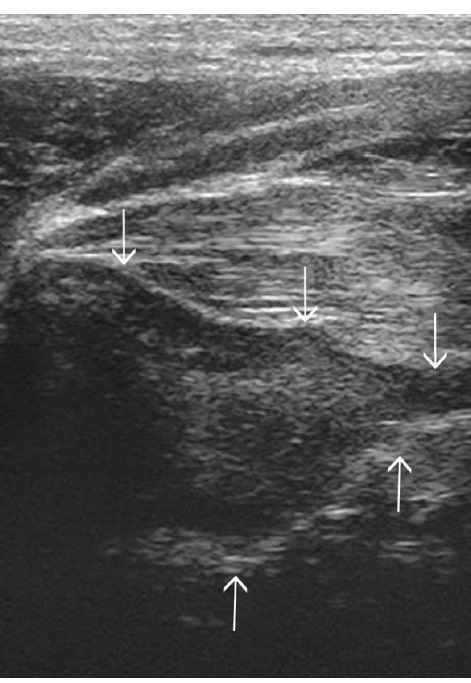

Fig 8: Comparison of echogenicity of the cricoarytenoideus lateralis and vocalis (arrows)

and cricoarytenoideus dorsalis (arrowheads) musculature. Horses with recurrent

laryngeal neuropathy have increased echogenicity and more homogeneous echogenicity

of the cricoarytenoideus lateralis and cricoarytenoideus dorsalis muscles. Dorsal plane

ultrasound images of the cricoarytenoideus lateralis muscle of (a) a horse with recurrent

laryngeal neuropathy and (b) a normal horse. Transverse plane ultrasound images of the

cricoarytenoideus lateralis and vocalis muscles of (c) a horse with recurrent laryngeal

neuropathy and (d) a normal horse. Dorsal plane ultrasound images of the cricoarytenoideus

dorsalis muscle of (e) a horse with recurrent laryngeal neuropathy and (f) a normal horse. In

the dorsal plane images, rostral is to the left and caudal is to the right and in the transverse

plane images, dorsal is to the left of the image and ventral is to the right